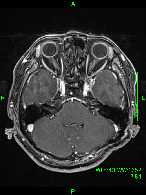

症例2) 31歳女性、頭蓋底部巨大髄膜腫、外科手術+放射線治療

<画像所見>

腫瘍はほとんど消失している。術後患者様は右眼瞼下垂、複視(動眼神経麻痺)生じたが、自宅退院された。